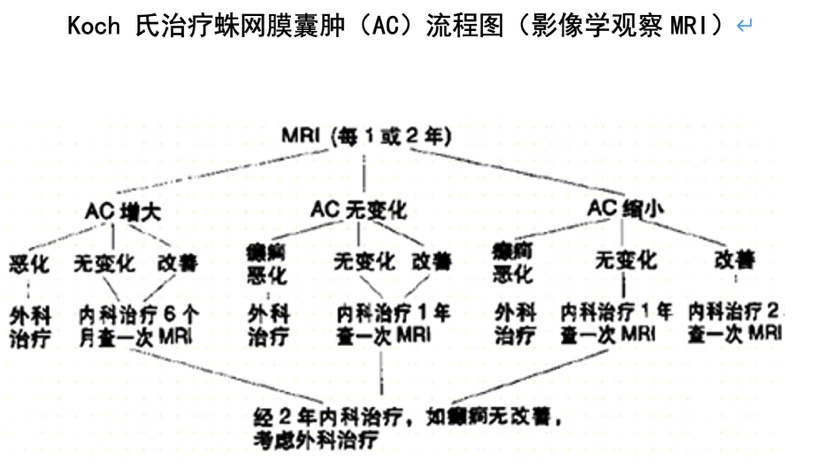

另外根据文献报道蛛网膜囊肿治疗Koch 氏观察流程表选择相应方案